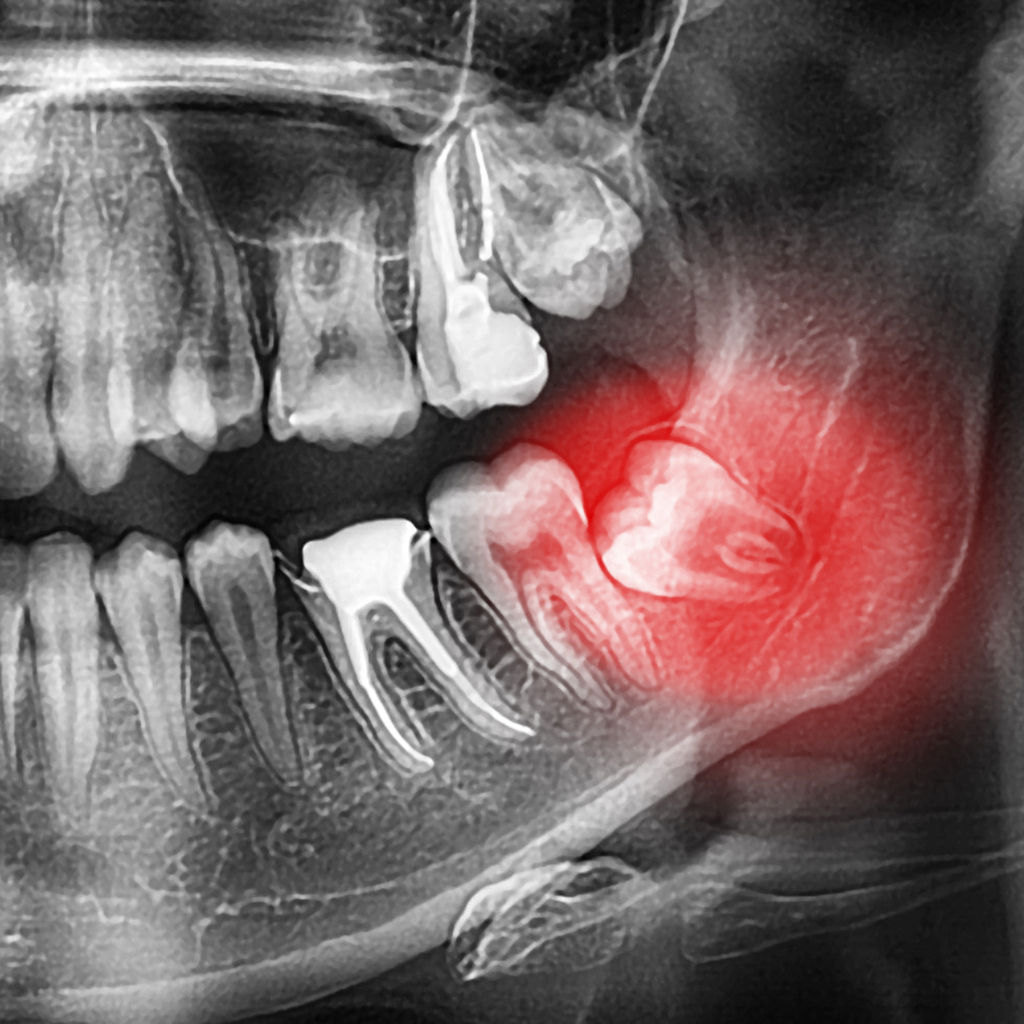

Durch die weit hinten liegende und sehr enge Position wird der Weisheitszahn oftmals zum Problem und muss gezogen werden (extraktion).

• nicht (retinierte) oder nur teilweise (teil-retinierte) durchgebrochene Weisheitszähne

• schiefe (verlagerte) Weisheitszähne, welche sehr häufig Durck auf die Nachbarzähne ausüben. Dies kann zu Zahnverschiebungen und Wurzelschädigungen führen.

Bei abrakazahbra prüfen wir die Situation und die Behandlungsoptionen eingehend mit dem Patienten. Im Falle einer notwendigen Entfernung eines oder mehreren Weisheitszähne wird ein DVT (digitales Röntgenbild) erstellt und von unserem Fachzahnarzt Oral- oder Kieferchirurgie geprüft und geplant. In den meisten Fällen wird eine oralchirurgische Operation zur Entfernung der Weisheitszähne empfohlen.